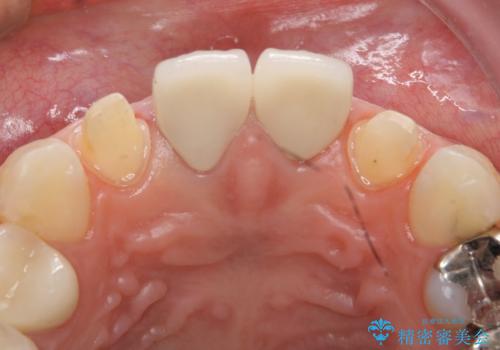

- 上顎の前から2番目の歯の古い樹脂をセラミックにしたいといらっしゃった方の症例です。

古い樹脂を除去後、オールセラミッククラウンによる補綴を行いました。

- オールセラミッククラウン…¥100,000×2、仮歯…¥10,000×2費用は治療当時の料金となります